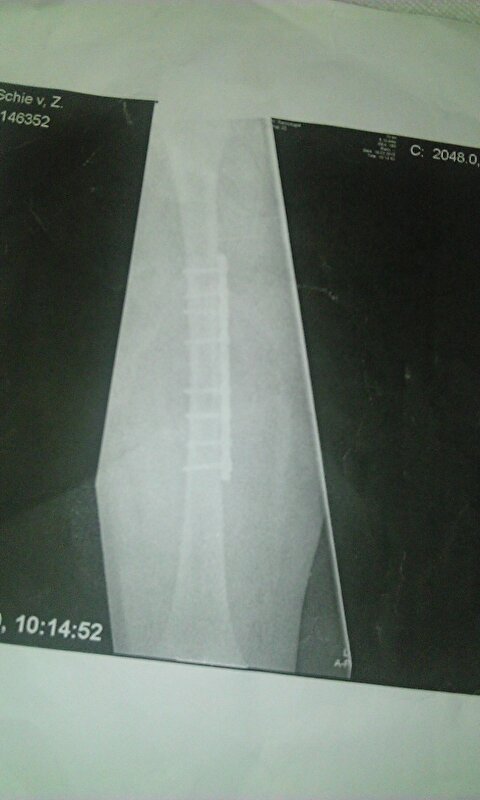

Wel druk aan het revalideren, kan ook belasten maar de afwikkeling bij het lopen lukt niet goed. Nog steeds wel pijn bij het lopen. Loop nog met twee krukken en af en toe in huis met 1 kruk. Ben in ziekenhuis dmv pin, plaatje en schroeven weer aan elkaar gezet. zorg dat je je voet zoveel mogelijk beweegt...dat scheelt straks enorm.